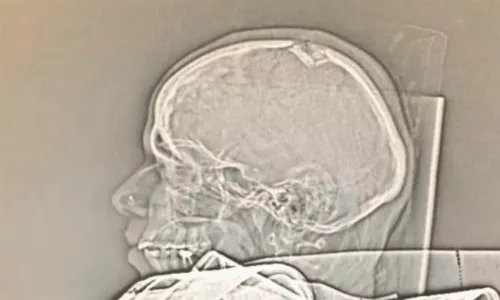

Exame mostra lesão na cabeça de grávida |  Foto: Reprodução TV Tribuna

A grávida atingida por um pedaço de concreto que se desprendeu de um poste, na Praia de Itaparica, em Vila Velha, sofreu afundamento do crânio e vai ser submetida a uma cirurgia na cabeça ainda nesta segunda-feira (04). O bebê não corre risco.

O marido dela informou para a TV Tribuna/SBT, que a mulher passou por exames que constataram que ela sofreu afundamento do crânio e isso estaria pressionando o cérebro dela. Por essa razão, a empresária vai precisar passar por uma cirurgia na cabeça ainda nesta segunda.

O marido revelou ainda que a fratura na cabeça também estaria comprometendo os movimentos das pernas de Clesiane. O bebê, porém, não corre risco.